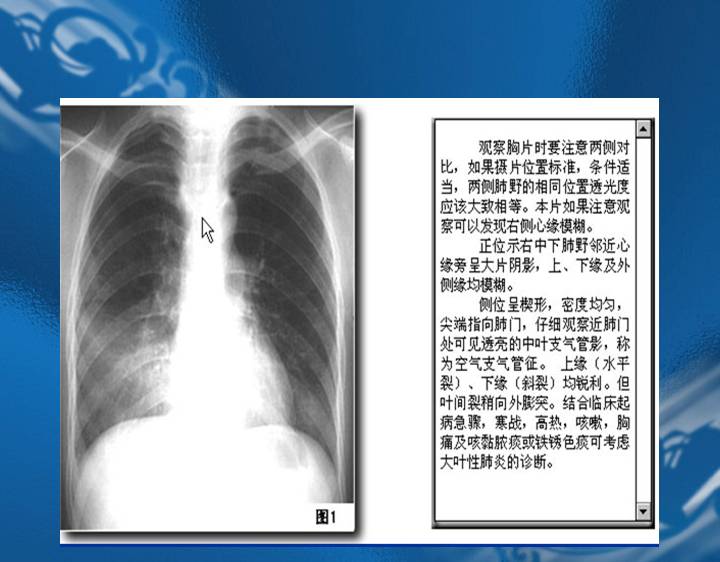

执业医师资格考试“实践技能”影像学辅导资料